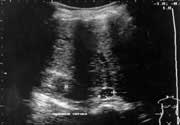

Анализ наших наблюдений свидетельствует, что правильный диагноз был поставлен 22 больным из 23 (95,6%). У одной больной с клиникой синдрома Иценко-Кушинга при эхоскопии было выявлено в области верхнего полюса правой почки эхопозитивное образование небольших размеров (30-35 мм), которое имело однородную внутреннюю эхоструктуру, четкие и ровные контуры и было расценено как доброкачественная опухоль надпочечника. Компьютерная томография не проводилась, так как имелась типичная клиническая картина синдрома Иценко-Кушинга, сопровождавшаяся клинико-лабораторными изменениями в крови и мочи. Во время операции была обнаружена  очаговая макроузловая гиперплазия надпочечника, которая подтвердилась при гистологическом исследовании удаленного образования (Рис. 2).

Увеличить

Рис. 2. Очаговая макроузловая гиперплазия надпочечника.

Согласно литературным данным (4,5,7) различают диффузную и очаговую гиперплазию надпочечников. Очаговая гиперплазия делится на микро- и макроузловую. По ультразвуковым признакам очаговую гиперплазию практически невозможно отличить от опухолей надпочечника, так что в данном случае наше заключение не может считаться диагностической ошибкой.